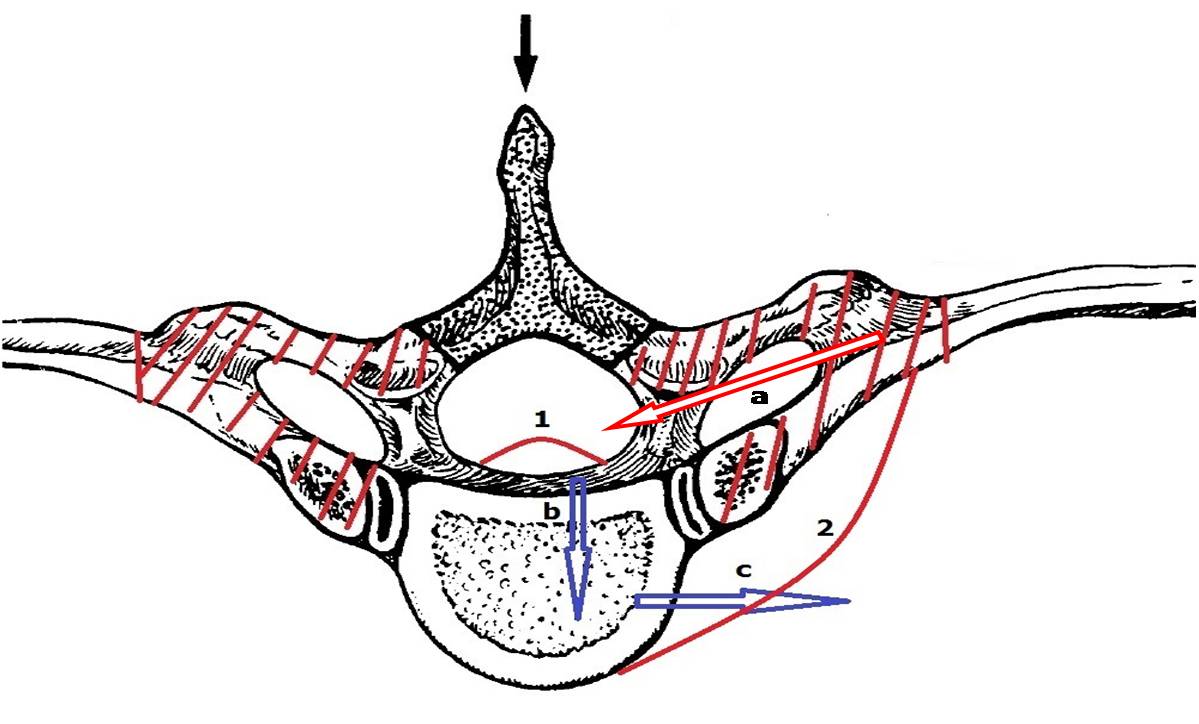

2. 手术方法:所有手术均在气管插管全麻下进行。麻醉满意后将患者置于俯卧位,胸前及双髂前垫枕,腰部稍后弓,腹部悬空。(1)手术切口和显露:依体表解剖标志结合影像学定位或体表放置金属标志行透视定位,来确定手术节段平面之所在;以此为中心行皮肤纵行切口,切口长度以分别包括头、尾侧的1~3节椎骨为宜。骨膜下剥离显露棘突、双侧椎板、关节突关节或肋横突关节和横突。(2)椎弓根钉道准备和螺钉植入:于椎间盘突出的相邻椎节,常规方法置入固定用的椎弓根螺钉,并经术中透视核实其固定节段无误且位置良好。(3)椎管后壁切除及后方椎间盘切除术:于双侧关节突关节的中线处纵向开槽,使用高速磨钻逐步向前磨透骨性结构,将椎管后壁以“揭盖式”整块切下。若同时还合并有黄韧带骨化,则一并予以切除。然后,以神经拉钩轻轻将硬膜牵向对侧,常规方法行突出椎间盘的后外侧纤维环切开、髓核摘除。此时,切记不要勉强行突出于硬膜腹侧正中部分的椎间盘切除,以免在切除过程中造成硬膜和神经的损伤。(4)极外侧入路:行残余的关节突关节切除后,充分显露突出椎间盘椎间隙的外侧缘,保护好椎间孔内穿行的神经根。在“安全三角区”(图1a, 1b)内,尽可能以与脊柱矢状面相垂直的方向经突出椎间盘的正侧方行椎间隙内残余的椎间盘组织切除。此时,尤其是合并“硬性突出”的椎间盘已呈一中空的“硬壳”,使用窄的快骨刀切断“硬壳”的基底部(即与椎体相连处),再以神经剥离子仔细分离其与硬膜间的粘连,将该游离“硬壳”轻轻压陷至已被掏空的椎间隙内,用髓核钳将其取出。如果对侧尚有残留的“硬壳”,同法处理对侧,完成彻底减压。(5)椎体间融合及椎弓根固定:将减压过程中切下的骨质经修理后植于椎体间,同时放置充填好碎骨的肾形椎间融合器(TLIF Cage)一枚。再次术中透视核实Cage位置无误后,遂经椎弓根螺钉行脊柱后方加压,一方面夹紧椎间融合器,同时也纠正了脊柱局部的后凸角度,进而达到椎管内神经结构的二次减压功效。

图1a 经后方极外侧入路手术横截面示意图,阴影部分为传统正后方切除范围,红色区域为改良手术增加切除范围,曲线1为突出椎间盘,曲线2为向后牵拉之胸膜,箭头a为手术入路方向,箭头b,c所示为间盘切除方向